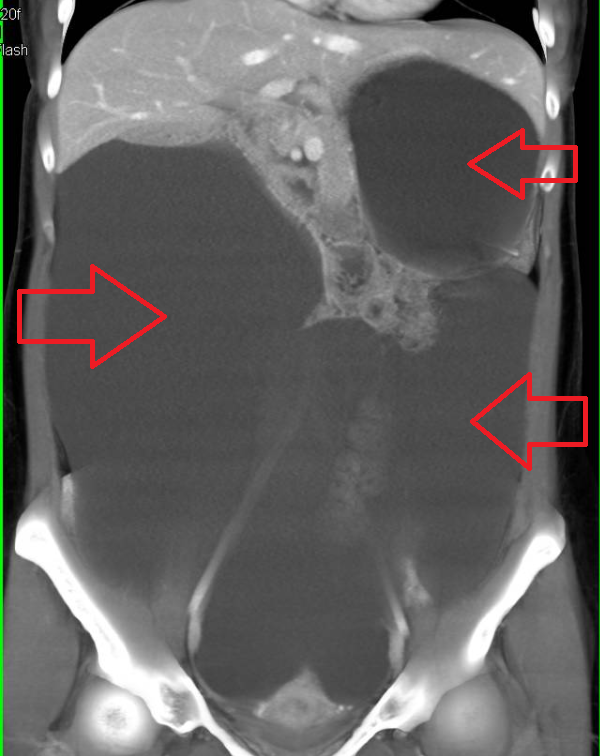

Красные стрелки указывают на жидкость, занимающую на представленной компьютерной томографии большую часть брюшной полости. Печень и селезенка отдавлены жидкостью кверху, в этой ситуации также происходит компрессия нижних долей легких, может возникнуть дыхательная недостаточность.